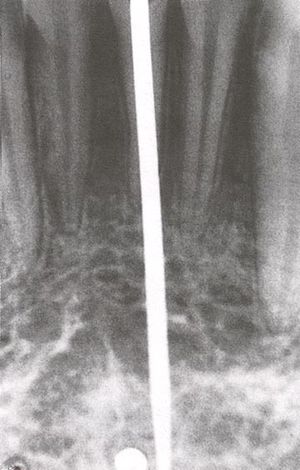

صورة شعاعية لغرسة السن.

While studying bone cells in a rabbit femur using a titanium chamber, Branemark was unable to remove it from bone. His realization that bone would adhere to titanium led to the concept of osseointegration and the development of modern dental implants. The original xray of the chamber embedded in the rabbit femur is shown (made available by Branemark).